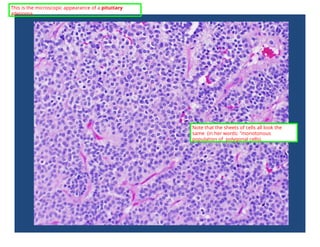

This is the microscopic appearance of a pituitary

adenoma.

Note that the sheets of cells all look the

same (in her words: "monotonous

population of polygonal cells).